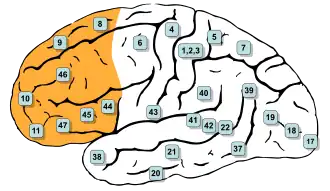

In contrast to the traditional view, more recent approaches analyze the mind in terms of mental modules rather than faculties.[46] A mental module is an inborn system of the brain that automatically performs a particular function within a specific domain without conscious awareness or effort. In contrast to faculties, the concept of mental modules is normally used to provide a more limited explanation. It is typically restricted to certain low-level cognitive processes without trying to explain how they are integrated into higher-level processes such as conscious reasoning.[47][e] Many low-level cognitive processes responsible for visual perception have this automatic and unconscious nature. In the case of visual illusions like the Müller-Lyer illusion, the underlying processes continue their operation and the illusion persists even after a person has become aware of the illusion, indicating the mechanical and involuntary nature of the process.[49] Other examples of mental modules concern cognitive processes responsible for language processing and facial recognition.[50]

Another approach to the relation between mind and matter uses empirical observation to study how the brain works and which brain areas and processes are associated with specific mental phenomena.[87] The brain is the central organ of the nervous system and is present in all vertebrates and the majority of invertebrates. The human brain is of particular complexity and consists of about 86 billion neurons, which communicate with one another via synapses.[88] They form a complex neural network and cognitive processes emerge from their electrical and chemical interactions.[89] The human brain is divided into regions that are associated with different functions. The main regions are the hindbrain, midbrain, and forebrain.[90] Many biological functions associated with basic survival are the responsibility of the hindbrain and midbrain. Higher mental functions, ranging from thoughts to motivation, are primarily localized in the forebrain.[91]

The primary operations of many of the main mental phenomena are located in specific areas of the forebrain. The prefrontal cortex is responsible for executive functions, such as planning, decision-making, problem-solving, and working memory.[92] The sensory cortex processes and interprets sensory information, with different subareas dedicated to different senses, like the visual and the auditory areas. A central function of the hippocampus is the formation and retrieval of long-term memories. It belongs to the limbic system, which plays a key role in the regulation of emotions through the amygdala. The motor cortex is responsible for planning, executing, and controlling voluntary movements. Broca's area is a separate region dedicated to speech production.[93] The activity of the different areas is additionally influenced by neurotransmitters, which are signaling molecules that enhance or inhibit different types of neural communication. For example, dopamine influences motivation and pleasure while serotonin affects mood and appetite.[94]